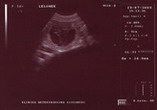

BAILY przeszła kontrolne badania i USG, które potwierdziło, że jest w ciąży. Ciąża przebiega prawidowo z czego się bardzo cieszymy. Maluchy urodzą się pod koniec Sierpnia. Ojcem miotu jest nasz BART.

Na zdjęciu USG, komora zarodkowa z widocznym płodem